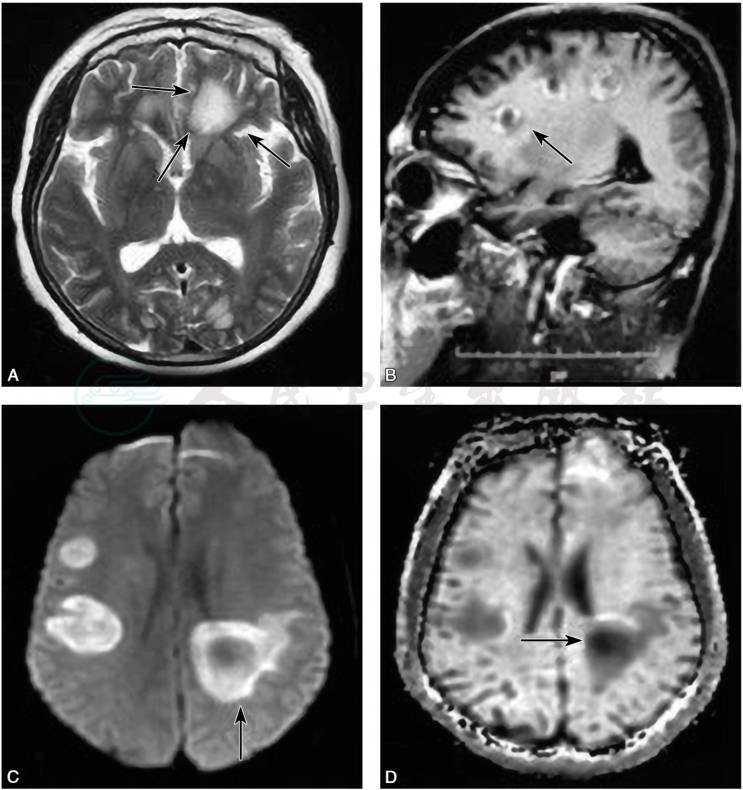

TIDD在脑MRI显示的病灶常比CT的范围要大,水肿也更明显,T1WI、T2WI多为高信号,其中,70%~100%的患者T2WI为高信号,边界较清楚,部分伴T2低信号边缘(图5A)。TIDD多有占位效应(图6A),但其程度多不及脑肿瘤,病灶周围多可见水肿带。急性或亚急性期,以细胞源性水肿为主,弥散加权成像(diffusion weighted imaging,DWI)多为高信号(图5C、D),经激素规范治疗后,病灶多在数周内逐渐缩小或消散。

图5TIDD“云片状”病灶及环形强化

A.病灶周边低信号边缘(箭头所指);B.病灶呈“C”形强化(箭头所指)。双侧侧脑室旁病灶弥散受限,表现为C.DWI高信号;D.ADC低信号

引自:神经病学:全2册.第3版.ISBN:978-7-117-31406-0.主编:

图6TIDD病灶占位效应

A.右侧额叶皮质下团块状长T2异常信号,占位效应明显,病灶周围指压状水肿显著;B.矢状位T1WI增强示:右侧病灶呈多发线状以及结节样强化,病灶内扩张的静脉血管呈长轴垂直于侧脑室的“梳齿状”强化(箭头所指)

2)MRI增强:

因血脑屏障的破坏,TIDD急性期与亚急性期在钆喷酸葡胺(Gd-DTPA)增强时,表现为结节样、开环样、闭环样、火焰状等不同形式的强化。其中,“开环样”强化(也有称“C”形强化,图5B)最具特征,即断“C”或开环形强化。另外,部分TIDD MRI增强扫描可见垂直于脑室的扩张的静脉影,呈“梳齿样”结构(刘建国等,2014)(图6B),急性期与亚急性期多见,该特点对于TIDD的诊断具有一定特异性,脑肿瘤无此特点。